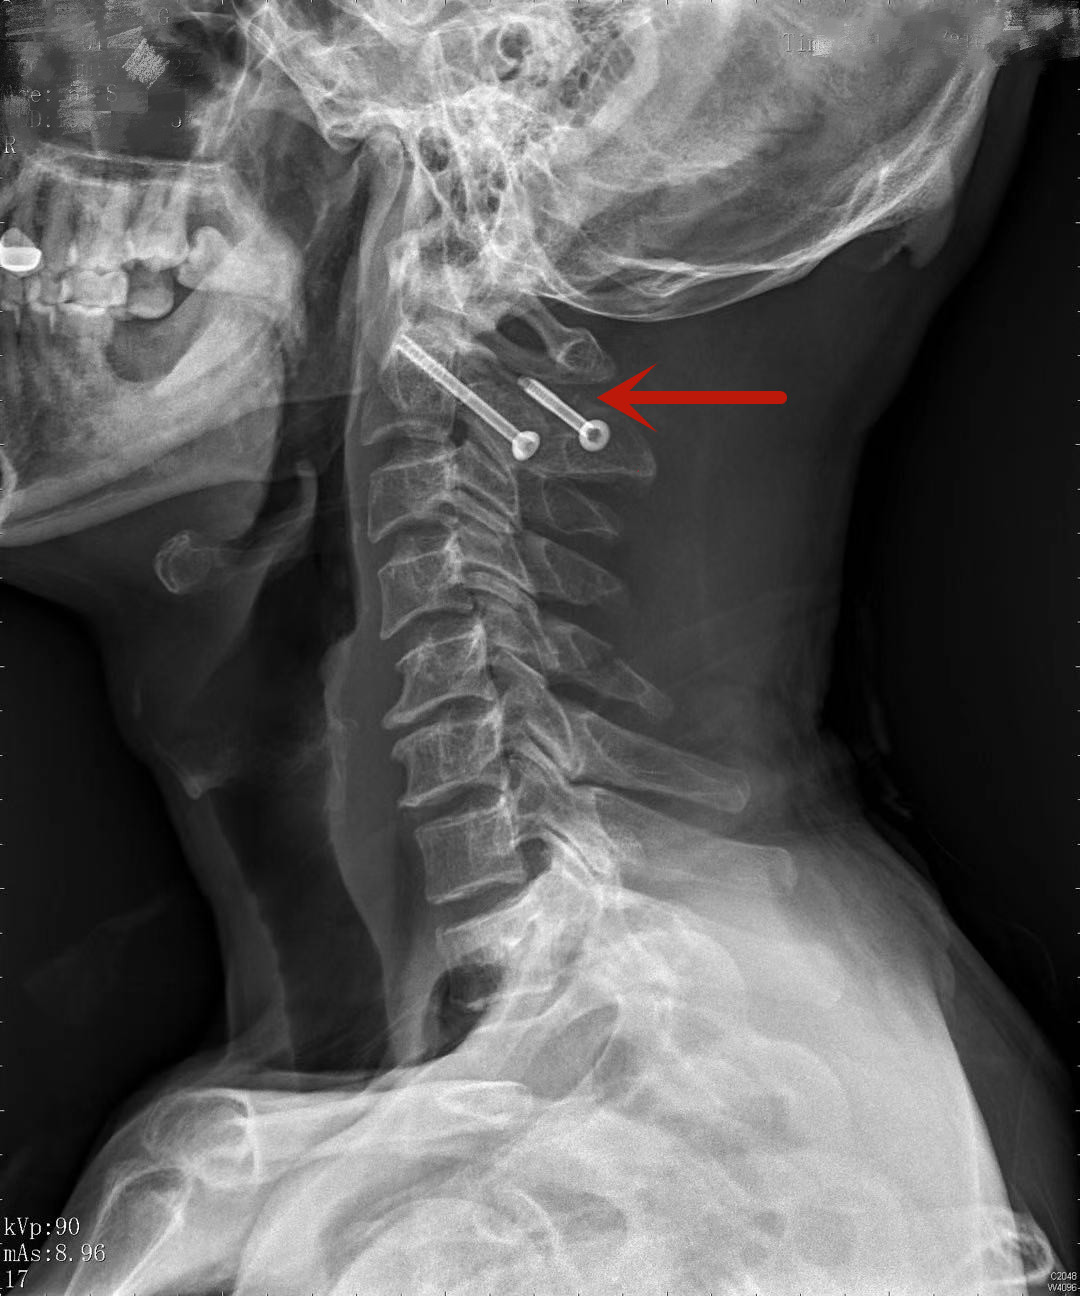

患者术后复查的影像资料显示螺钉精准地植入骨折块中

在手术台之外的控制台,是机器人的“大脑”,肖嵩华在此规划机器人手臂的置钉方案,手术过程采用“导航+机械手臂”的方式,通过术中影像资料精准定位骨折部位,规划导航路线。医师使用机械手臂按照预订路线,可直接并精准定位至骨折位置为患者进行手术,减少了不必要的开口创伤;机器人手臂同时避免了人工操作时的手部颤动,提高了手术精准度,缩短了手术与恢复时间;仅微创植入两枚空心钉就达到了固定效果,术后第二天患者即可佩戴颈托下地活动,不到一周,患者已达到出院标准。